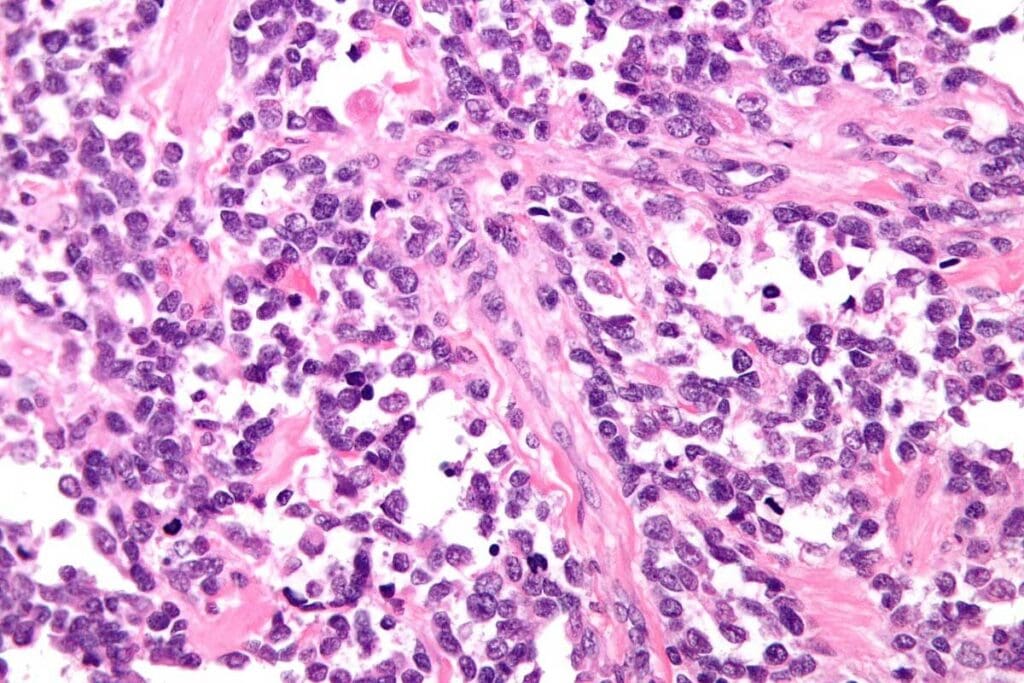

Alveolar rhabdomyosarcoma is a soft tissue sarcoma that starts in muscle cells. It looks like lung tissue, which is why it’s called alveolar. It’s part of the rhabdomyosarcoma family, with alveolar and embryonal being the main types.

Doctors sort rhabdomyosarcoma by how it looks under a microscope. Alveolar rhabdomyosarcoma has a special pattern. Knowing this helps doctors figure out how to treat it.

Biopsy and Pathological Analysis

A biopsy is key to confirming alveolar rhabdomyosarcoma. A sample of the tumor is taken and looked at under a microscope. Pathologists check for the special features of alveolar RMS, like its genetic makeup.